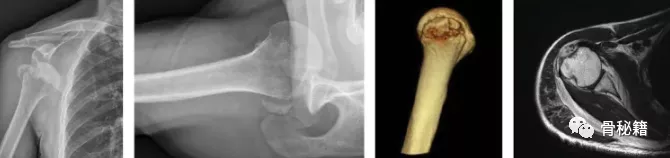

后路损伤机制 。 肩关节脱位的老年患者容易出现肩袖撕裂(注意 还是前脱位)

轴向图像显示 Bankart 损伤 , 冠状图像显示中等大小的全层肩袖撕裂

患有急性脱位的患者中 , 详细的 X 线平片包括真实的前后位、修正的轴向和肩胛侧位面 。 应排除肩部周围的相关损伤(例如大结节骨折)和上肢的其他损伤 。 脱位复位后 , 必须重复检查以确认关节的一致性并排除其他损伤 。 如果怀疑有相关骨折 , 则应进行 3D CT 扫描 。

MRI 或 MR 关节造影可能有助于确定相关肩袖撕裂、Bankart 病变和/或其他前骨或囊唇病变(例如前囊撕裂)的大小 。 当患者在脱位复位后仍表现出持续的虚弱、疼痛或不稳定时 , 建议进行 MRI